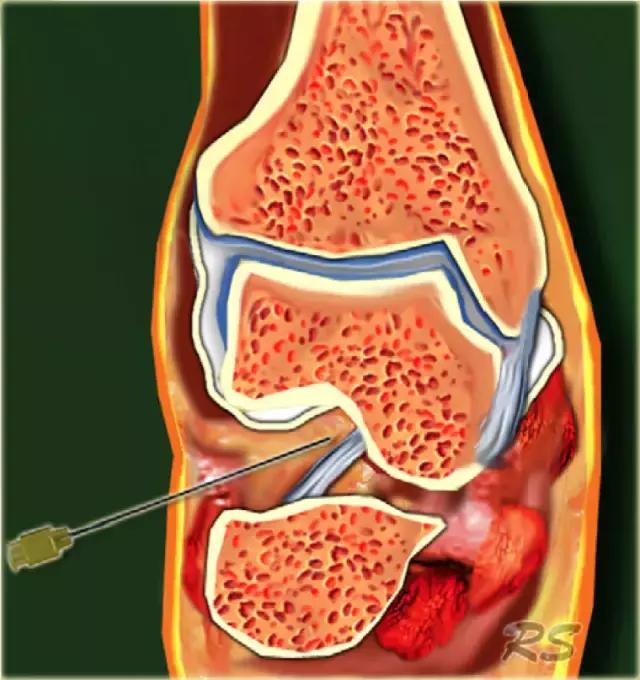

膝关节

膝关节CT或MR关节镜的适应症是手术后半月板的评估,查询关节内体,评估骨软骨病变的稳定性和评价关节软骨。如果需要治疗,则注射药物,例如皮质类固醇和/或局部麻醉剂。对于注射,我们不使用超声引导,但使用标准的“盲法”程序,使用侧向中髌方法在髌骨后面引入针(21号,50mm)。髌骨是单侧和从中间横向侧面朝向由左食指指示的髌骨的中心瞄准引入的针。针水平地向后引导到髌骨的中心,直到与外侧髌骨面或外侧股骨髁接触,并且当被感觉到在关节中时,注射造影剂40mL.CT或MR此前可以选择适用上述髌骨从而迫使从髌凹陷反差进入关节间隙适当紧的绷带。